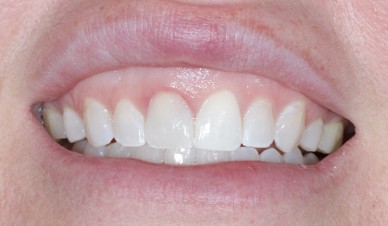

Extensive training and experience give prosthodontists a unique understanding of restoring the dynamics of a smile and healthy mouth with the creation of tooth prostheses. Becoming a prosthodontist requires an additional three years of specialty training after obtaining a DMD (Doctor of Dental Medicine) or DDS (Doctor of Dental Surgery) degree.

As a dentist specializing in Prosthodontics, Dr. Yepez’ philosophy has always been driven by providing excellent treatment to her patients in a caring and comfortable atmosphere, emphasizing in prevention and education. Her goal is to exceed the expectations of her patients by providing appropriate and quality care allowing them to make an educated decision about their dental treatments.